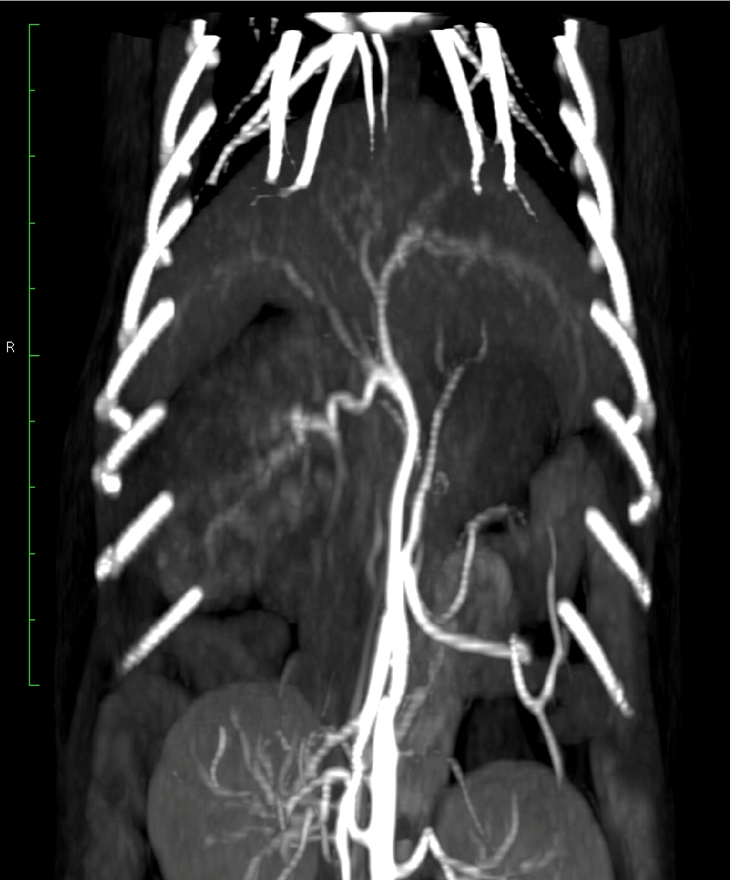

CT(第2病日)

肝動脈尾状葉枝が栄養血管門脈血の流入は確認されず

尾状葉由来5cm大

動脈相

門脈相

CT MIP

【診断・治療方針】

腹腔内腫瘤の破裂による非外傷性出血

― 腹腔内腫瘤は肝尾状葉由来 (Φ5cm)

腫瘤は動脈相で早期膿染

― 肝動脈尾状葉枝が栄養血管